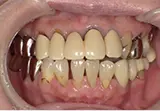

| 年齢/性別 | 60代女性 |

| 主訴 | 前歯が前に出てきた |

| 治療内容 | 全体的に歯周病やむし歯、根の治療(ヘミセクション)を実施。右上の歯にはサイナスリフト術を行い、骨の回復を待った後、半年後に2本のインプラントを埋入しました。 |

| 治療期間 | 9か月 |

| 費用 | 1,298,000円税込 |

| リスク・副作用 | 炎症反応によって術後に腫れや副鼻腔炎が生じることがあります。その程度は、手術の範囲や方法によって異なりますが、多くの場合、時間の経過とともに徐々に治まります。

ごく稀に、下顎奥歯の外科手術後に、唇や顎に痺れを感じることがあります。 |